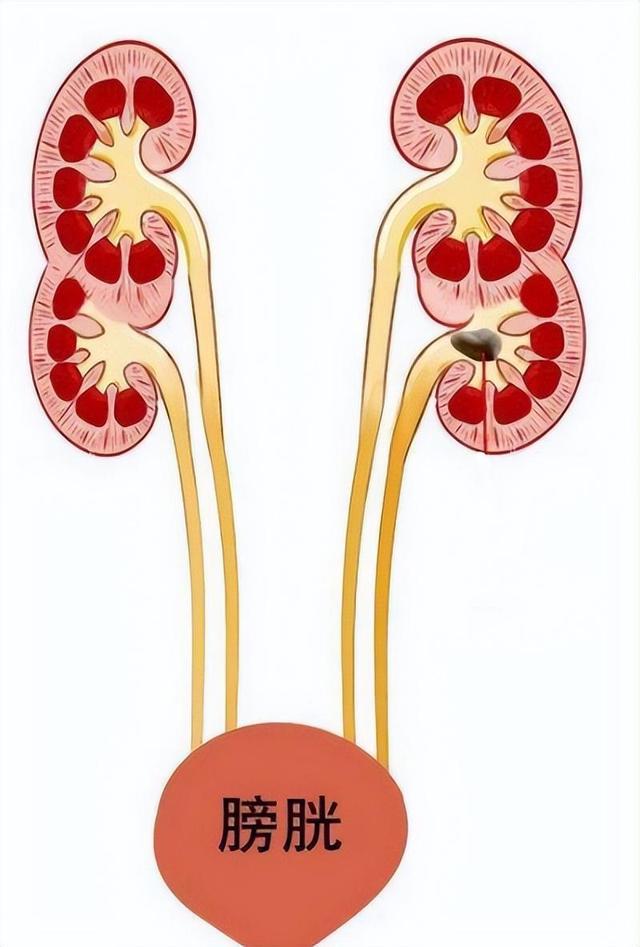

通常来讲,每个人都有两个肾,分别位于腹内的左右侧。而王开炼与众不同,他的左右两侧分别有两个肾,加一起一共有四个!这也能很好解释,为什么王开炼天生神力,举300斤的重物不在话下,同时还能“千杯不醉”了。

经过详细的检查后,梅医生认为,之所以王开炼体内的四个肾不显得“拥挤”,是因为他的肾比正常人小得多,每个只有婴儿拳头般大小。

同时,王开炼腰疼的原因也找到了,他的左上肾患有严重的肾积水,导致这一个肾的体积比另三个肾还大,这才出现了频繁腰疼的症状。

经过科学的诊断后,梅医生给出了自己的建议:“必须切掉这个‘坏了’的肾,否则造成合并感染,你另外三个肾也会受到影响。”